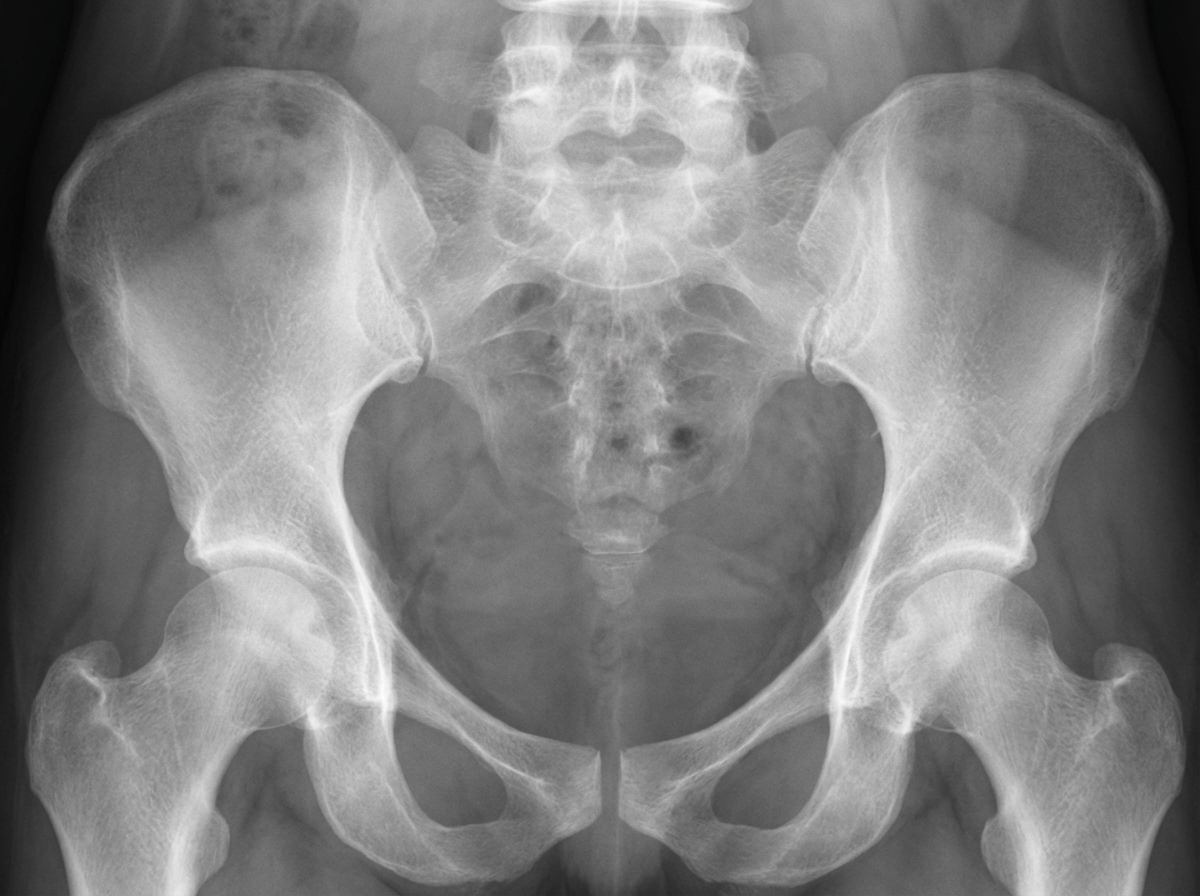

What type of pelvic appearance is this?

Explanation: ***Champagne glass pelvis*** - Characterized by **squared iliac wings**, **narrow pelvic inlet**, and **small sciatic notches**, creating a wine glass appearance on AP radiographs. - Commonly seen in **achondroplasia** and other skeletal dysplasias, representing abnormal bone development. *Corkscrew pelvis* - This is **not a standard radiological classification** term used in pelvic anatomy or radiology. - The term does not correspond to any recognized **pelvic morphological pattern** in medical literature. *Gynecoid pelvis* - Refers to the **normal female pelvic shape** in the **Caldwell-Moloy classification** with rounded pelvic inlet. - Features include **wide pelvic inlet**, **curved sacrum**, and **wide pubic arch**, optimal for childbirth. *None of the above* - The **champagne glass pelvis** is a well-recognized radiological sign, making this option incorrect. - The characteristic appearance is pathognomonic for certain **skeletal dysplasias**, particularly achondroplasia.